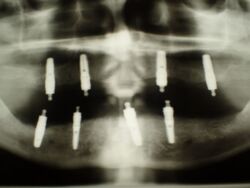

2007 wurde diese implantatgestützte Versorgung erstellt. Die 8 Implantate wurden allesamt hier inseriert und befinden sich bis heute, vollkommen unverändert in Funktion.

Hier eines der großewn Probleme, gerade im Bereich der Implantate, dass Implantathersteller insolvent werden, oder aber bestimmte Ersatzteile einer Produktlinie nicht mehr produziert werden.

Derartige Probleme können dann am Ende dazu führen, dass volkommen intakte Implantate mit erheblichen Knochenverlusten aus dem Kieferknochen herausgefräst, augmentiert und dann neue Implantate inseriert werden müssen.